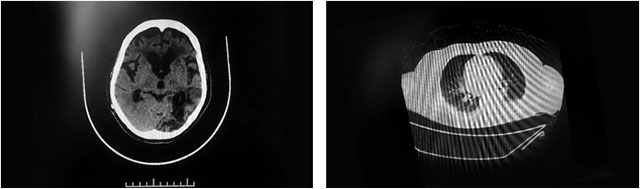

▲ 患者多發(fā)性腦梗,且肺部感染嚴(yán)重

7月23日,顧女士再次突發(fā)腦梗,這次就沒那么幸運,其左頸內(nèi)動脈、大腦中動脈嚴(yán)重閉塞,高達75%以上,隨后在救治醫(yī)院進行了腦血管造影+左頸動脈CTO病變血管成形術(shù)。不久,顧女士病情再次加重,其頭部CT提示:腦室擴張,又于8月14日全麻下行腦室—腹腔分流術(shù);之后又因肺部感染較重,咳痰較多、呼吸困難,于8月18日行氣管切開呼吸機輔助呼吸。